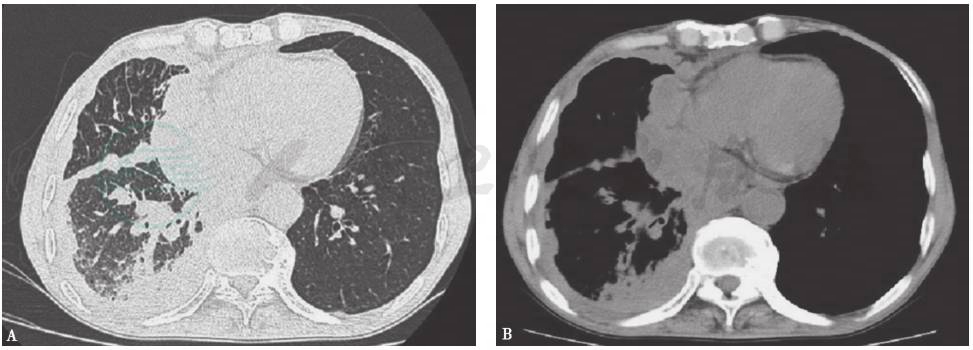

图2 胸膜间皮瘤影像学特点

胸部CT显示右侧胸膜弥漫性结节状增厚,累及肋胸膜、纵隔胸膜及叶间胸膜,右侧包裹性胸腔积液;右肺体积缩小伴肺膨胀不全。诊断恶性间皮瘤

图3 恶性胸腔积液影像学特点

胸部CT显示右肺上叶尖后段斑片影,边界模糊。右侧胸廓内缘与右肺之间可见包裹性胸腔积液,伴右侧胸膜局限性增厚。诊断右上肺癌